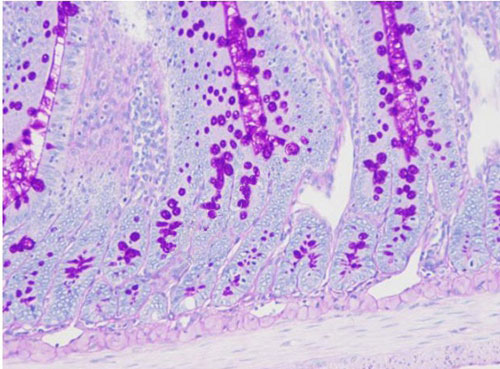

PAS染色又稱過(guò)碘酸雪夫染色,糖原染色。一般用來(lái)顯示糖元和其它多糖物質(zhì)。過(guò)碘酸能使細(xì)胞內(nèi)的多糖乙二醇基氧化成二醛,再與Schiff氏液的無(wú)色品紅結(jié)合,紅色,定位于胞漿上

實(shí)驗(yàn)結(jié)果展示:

PAS染色—小鼠腸

糖原、中性粘液物質(zhì)、軟骨基質(zhì)、植物的真菌和細(xì)胞壁、上皮的基膜等均呈紫紅色,細(xì)胞核淺藍(lán)色